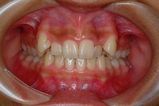

治療前 の 正面 です 動く矢印治療後 の 正面 です